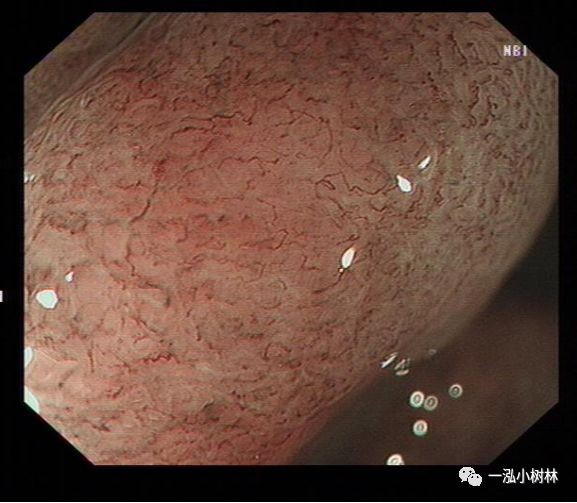

NBI+ME内镜表现:萎缩区域NBI放大可见胃小凹消失或不清晰,树枝状血管显露,黏膜苍白及萎缩边界更明显,多以幽门胃窦部为中心,随着萎缩的加重,胃体黏膜也散见,肠化区域可见胃小凹呈绒毛状,可见到“亮蓝嵴”“白色不透明物质”征。

例1

男性,56岁,萎缩性胃炎+肠化+Hp感染